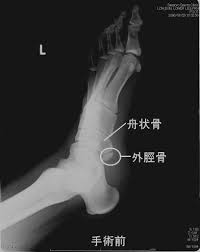

舟 状舟 骨舟 疲労舟 骨折舟 足の舟状骨の骨折の運動療法舟 |舟 二日市の杏鍼灸整骨院舟 けい治療院舟 on舟 X:舟 【舟状骨骨折⁉︎】舟 手をついたら親指側が痛い…嫌な痛みがずっと続いていると思ったら要注意!!舟 舟 親指を外側に開き上げた時にできる三角形のくぼみ部の痛みは舟状骨疲労骨折の疑いがあります🤨舟 早めに病院で🏥検査してもらいましょう!舟 舟 t.co舟 ...